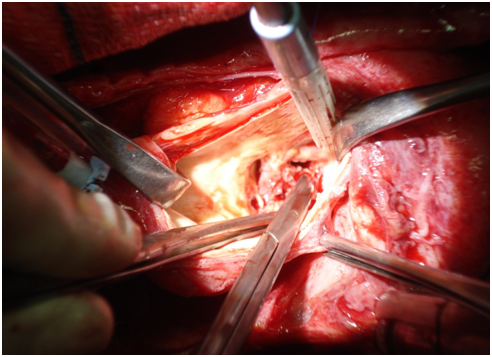

We presenting here a case of the patient with bicuspid aortic valve complicated with aneurysm of right sinus of valsalva. The aneurysm of sinus of valsalva was extracardiac and extending behind the main pulmonary artery and to the left. A 45years old Muslim male patient, carpenter by occupation was admitted with chief complaints of shortness of the breath and chest pain for 1 month. He was having orthopnoea and paroxysmal nocturnal dyspnoea and swelling of the feet. His vitals were stable with pulse rate 96/min, blood pressure 130/50mm Hg, and respiratory rate 14/min. On auscultation S1 was normal and S2 was soft with grade III/VI diastolic murmur in aortic area. Patient was properly investigated. ECG showed sinus rhythm and X-ray chest was showing cardiomegaly. Transthoracic echocardiography showed calcified bicuspid aortic valve, severe aortic regurgitation, grade II mitral regurgitation and that was appeared to be as dissecting flap in ascending aorta with 75% ejection fraction (Figure 1). Computed tomography chest was domne and it showed large pseudo-aneurysm of right sinus of Valsalva (Figures 2 & 3). Computed tomographic angiocardiography was done to define the lesion in the aorta accurately. Computed tomographic angiocardiography (Figures 4 & 5) revealed dysplastic aortic valve, para valvular aneurysmal sac communicating with aortic root as well as to left ventricle (? Pseudo-aneurysm). Routine investigations were done and patient was prepared for surgical intervention. Transoesophageal echocardiography was done in after induction of anaesthesia, which showed a large aneurysmal swelling behind the root of aorta. Conventional sternotomy was done. There were adhesions between pericardium and the heart. All adhesions were lysed. Aortotomy was done after institution of cardiopulmonary bypass. Bicuspid aortic valve and opening of the aneurysm were identified (Figure 6). Distorted, calcified aortic leaflets were excised and the opening of the aneurysm of sinus of valsalva was closed with Dacron patch from inside of the aorta (Figure 7). Aortic valve was replaced with sorin, bileaflet, mechanical valve, size 21 using interrupted ethibond, pladgeted sutures (Figure 8). Postoperative period was uneventful and patient was discharged on 7th postoperative day in good general condition. Patient is doing well in follow up visits.

Figure 6 After Aortotomy.